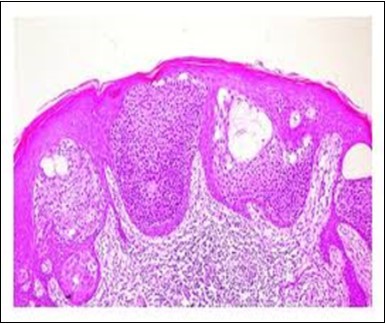

Figure 2.Epidermal projections lined with atypical and malignant epithelial cells in eccrine porocarcinoma (14).

Epidermal projections lined with atypical and malignant epithelial cells in eccrine porocarcinoma (14).